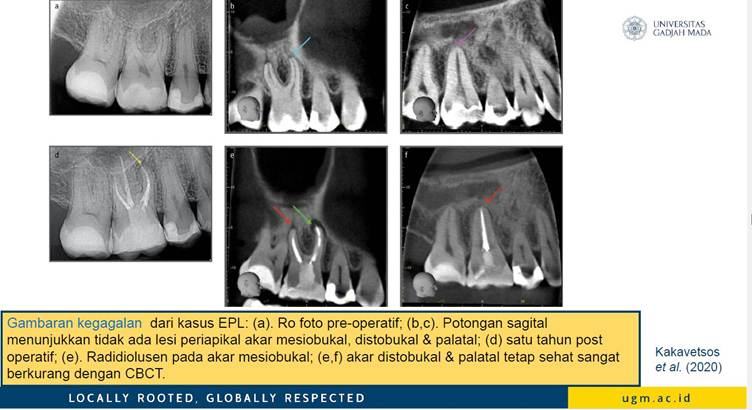

Diagnosis EPL memerlukan kombinasi pemeriksaan klinis, vitalitas pulpa, radiografi konvensional, dan pemindaian 3D menggunakan Cone Beam Computed Tomography (CBCT). CBCT memungkinkan identifikasi morfologi akar, kehilangan tulang, dan keterlibatan jaringan secara lebih presisi dibanding radiograf periapikal konvensional. Selain itu, uji mikrobiologis dengan Polymerase Chain Reaction (PCR) dan Next Generation Sequencing (NGS) membantu menentukan terapi antimikroba yang efektif.